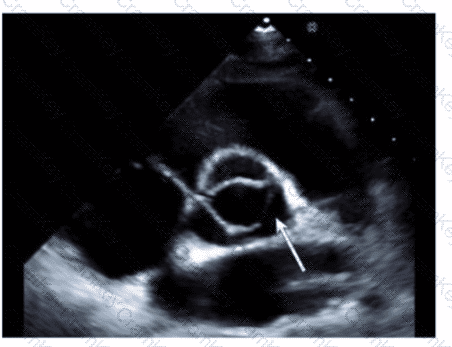

Which structure is indicated by the arrow on this image of a normal valve?

Questions 19

Options:

A.

Posterior leaflet

B.

Septal leaflet

C.

Non-coronary cusp

D.

Left coronary cusp